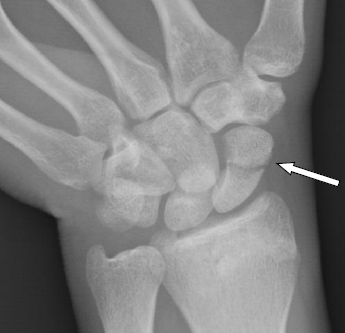

Diagnosis: Right scaphoid delayed union of the mid waist fracture

Types of Scaphoid Fractures: Scaphoid fractures can vary in location and severity. The most common type is a fracture of the waist of the scaphoid, but fractures can also occur at the proximal (near the forearm) or distal (near the hand) ends of the bone.

Diagnostic Challenges: Detecting scaphoid fractures can be tough, especially in the beginning, because they might not show up well on regular X-rays. This happens because the scaphoid bone has a unique blood supply that can be affected when it’s broken, making it heal slowly. Dr. Badia uses a special live X-ray technique called fluoroscopy to get a clearer picture and diagnose these fractures more accurately.